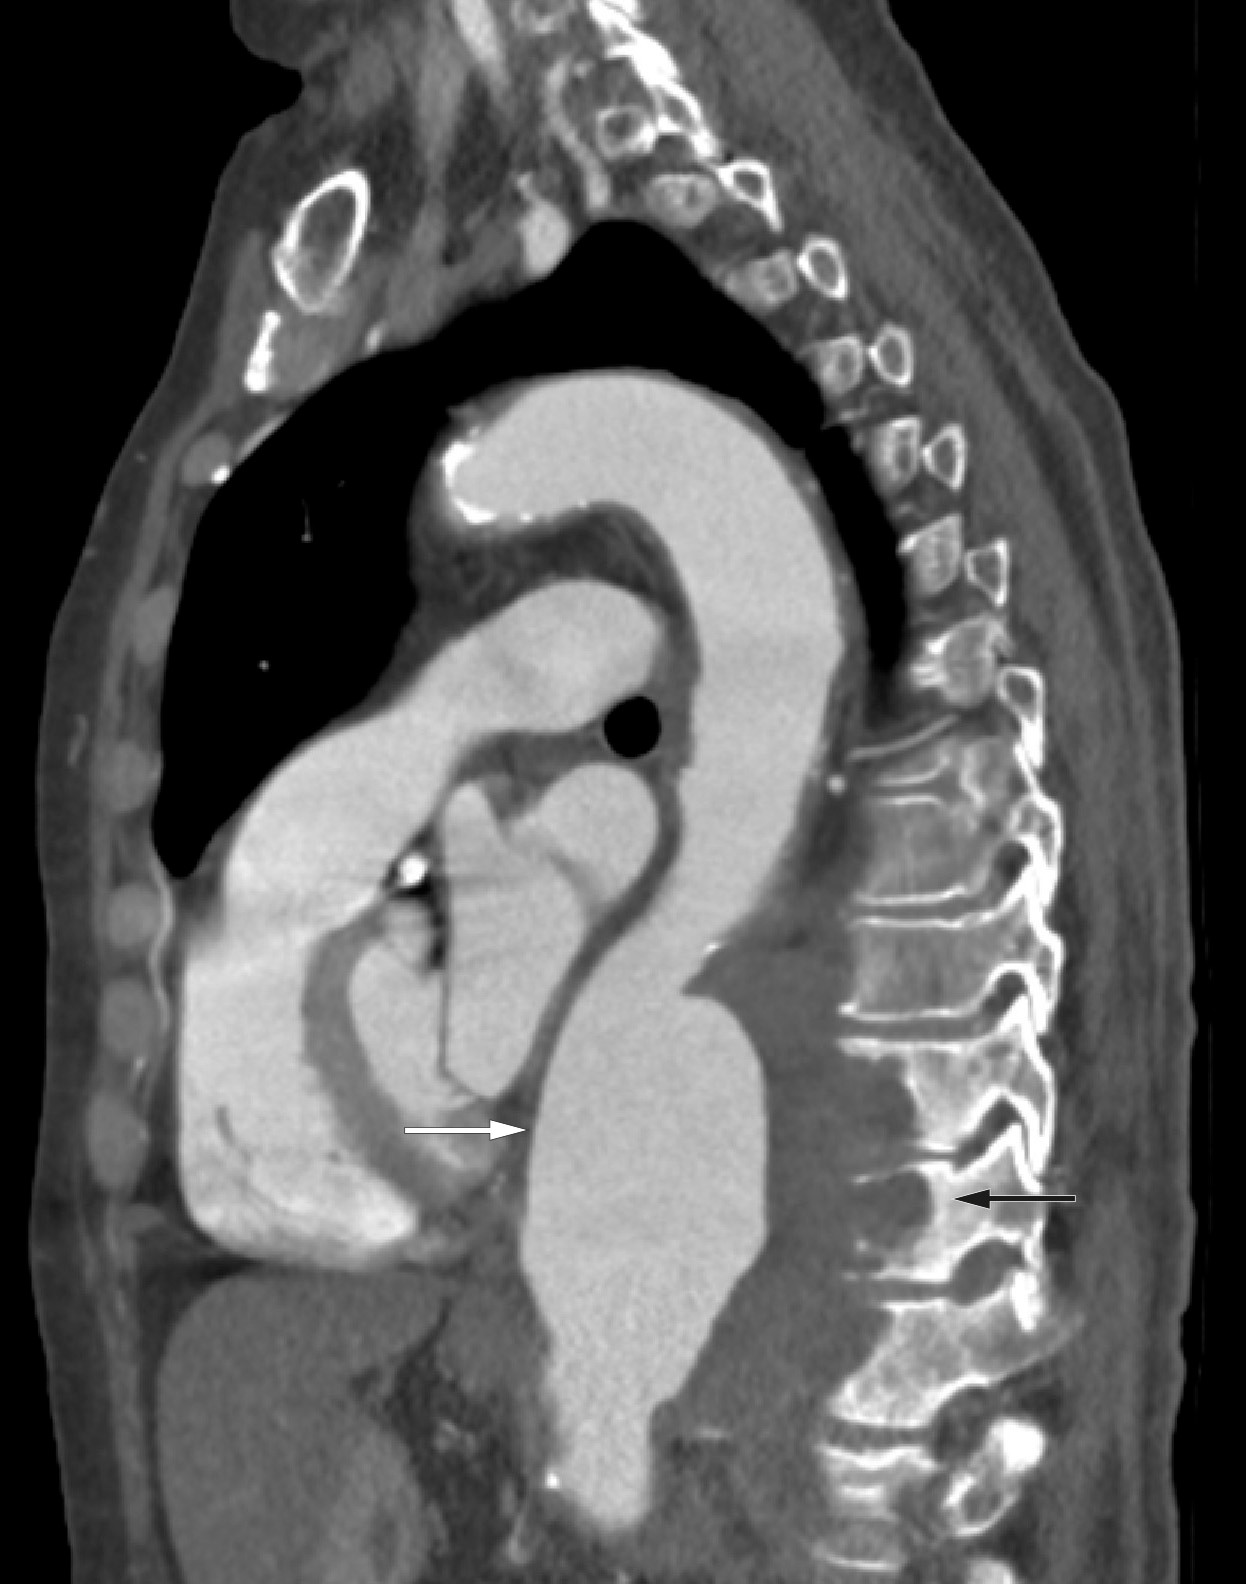

CT thorax viste et stort fusiformt, torakalt aneurisme i aorta descendens med største anteroposteriore diameter på 10,5 cm (figur 1). Funnet var radiologisk forenlig med et mykotisk aneurisme med destruksjon av tilliggende torakalcolumna. Det var ikke tegn til malignitet.